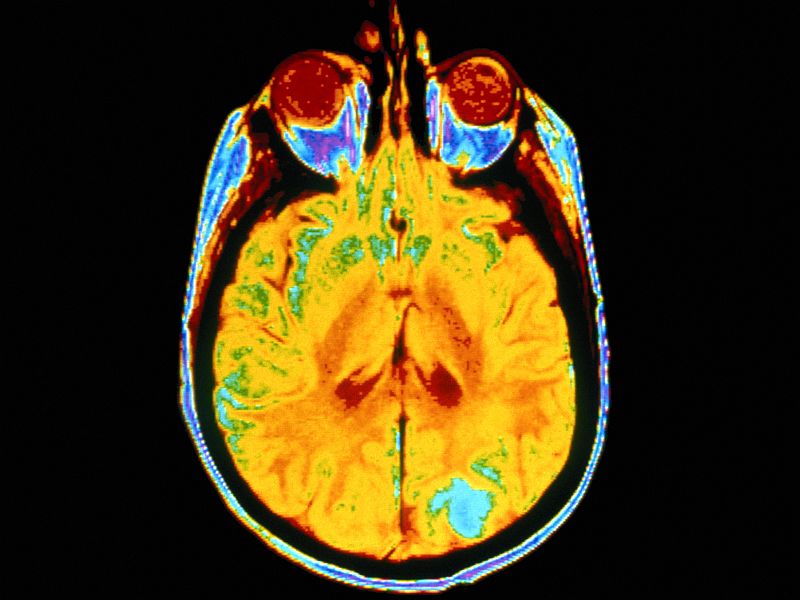

Immune-Based Therapy May Help When Melanoma Spreads to Brain

THURSDAY, July 12, 2018 (HealthDay News) — A type of therapy that harnesses the immune system is giving new hope to people battling a once hopeless cancer — melanoma that’s spread to the brain. New research involving more than 2,700 U.S. patients is confirming what specialists in the field haveContinue Reading